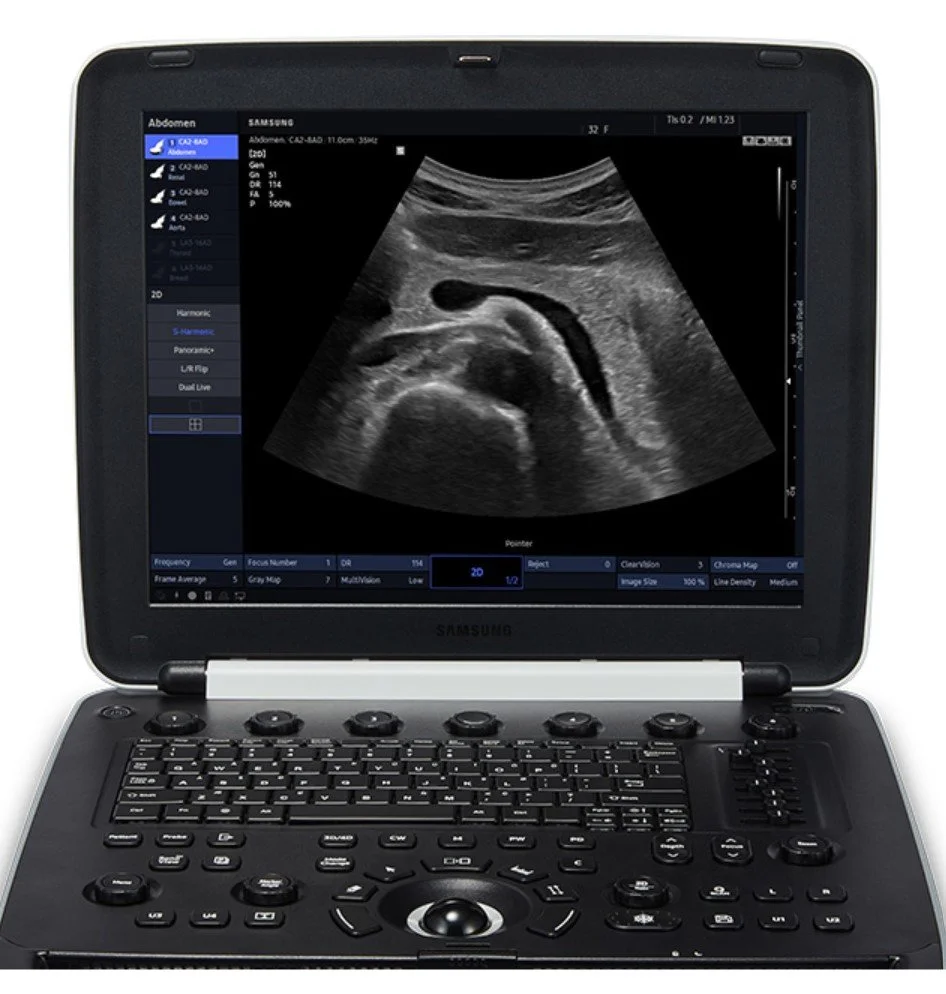

Ultrasound, Radiographs, CT, and MRI services provided by a board-certified veterinary radiologist.

Our mobile team comes to your practice and works with you to provide high quality results with diagnostic radiology services.